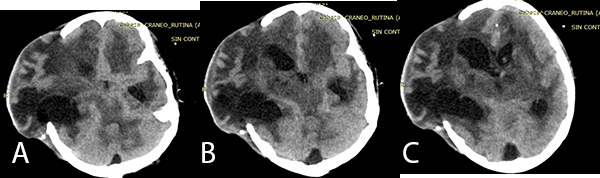

Imagen 2: (A), (B) y (C) TEM cerebral sin contraste en corte axial muestra leve dilatación ventricular con catéter de DVE, además de ligera asimetría entre hemisferios cerebrales.

El paciente no presentó mejoría del estado de conciencia, ingresando a Unidad de Cuidados Intensivos donde se evidencia hipertensión endocraneana refractaria, con mediciones de PIC mayores de 20 mmHg sostenida más de 30 minutos pese a tratamiento neurointensivo. Debido a ligera asimetría interhemisférica (Imagen 2) con hipo densidades sugerentes de edema cerebral frontal derecho es sometido a una Craniectomía Descompresiva.

Imagen 3: (A), (B), (C) TEM cerebral sin contraste cortes axiales previa a la fenestración endoscópica, se evidencia hidrocefalia asimétrica post colocación de DVE en el cuerno frontal izquierdo.

En la TBC del SNC se evidencia que se produce una reacción inflamatoria afectando las cisternas basales con obliteración de las mismas, evidenciándose en la TEM cerebral como exudados isodensos o hiperdensos tal como indica Bathla et al.(10) En la TEM cerebral (Imagen 3) del paciente se evidenció que las cisternas basales se encontraban obliteradas por imágenes ligeramente hiperdensas.